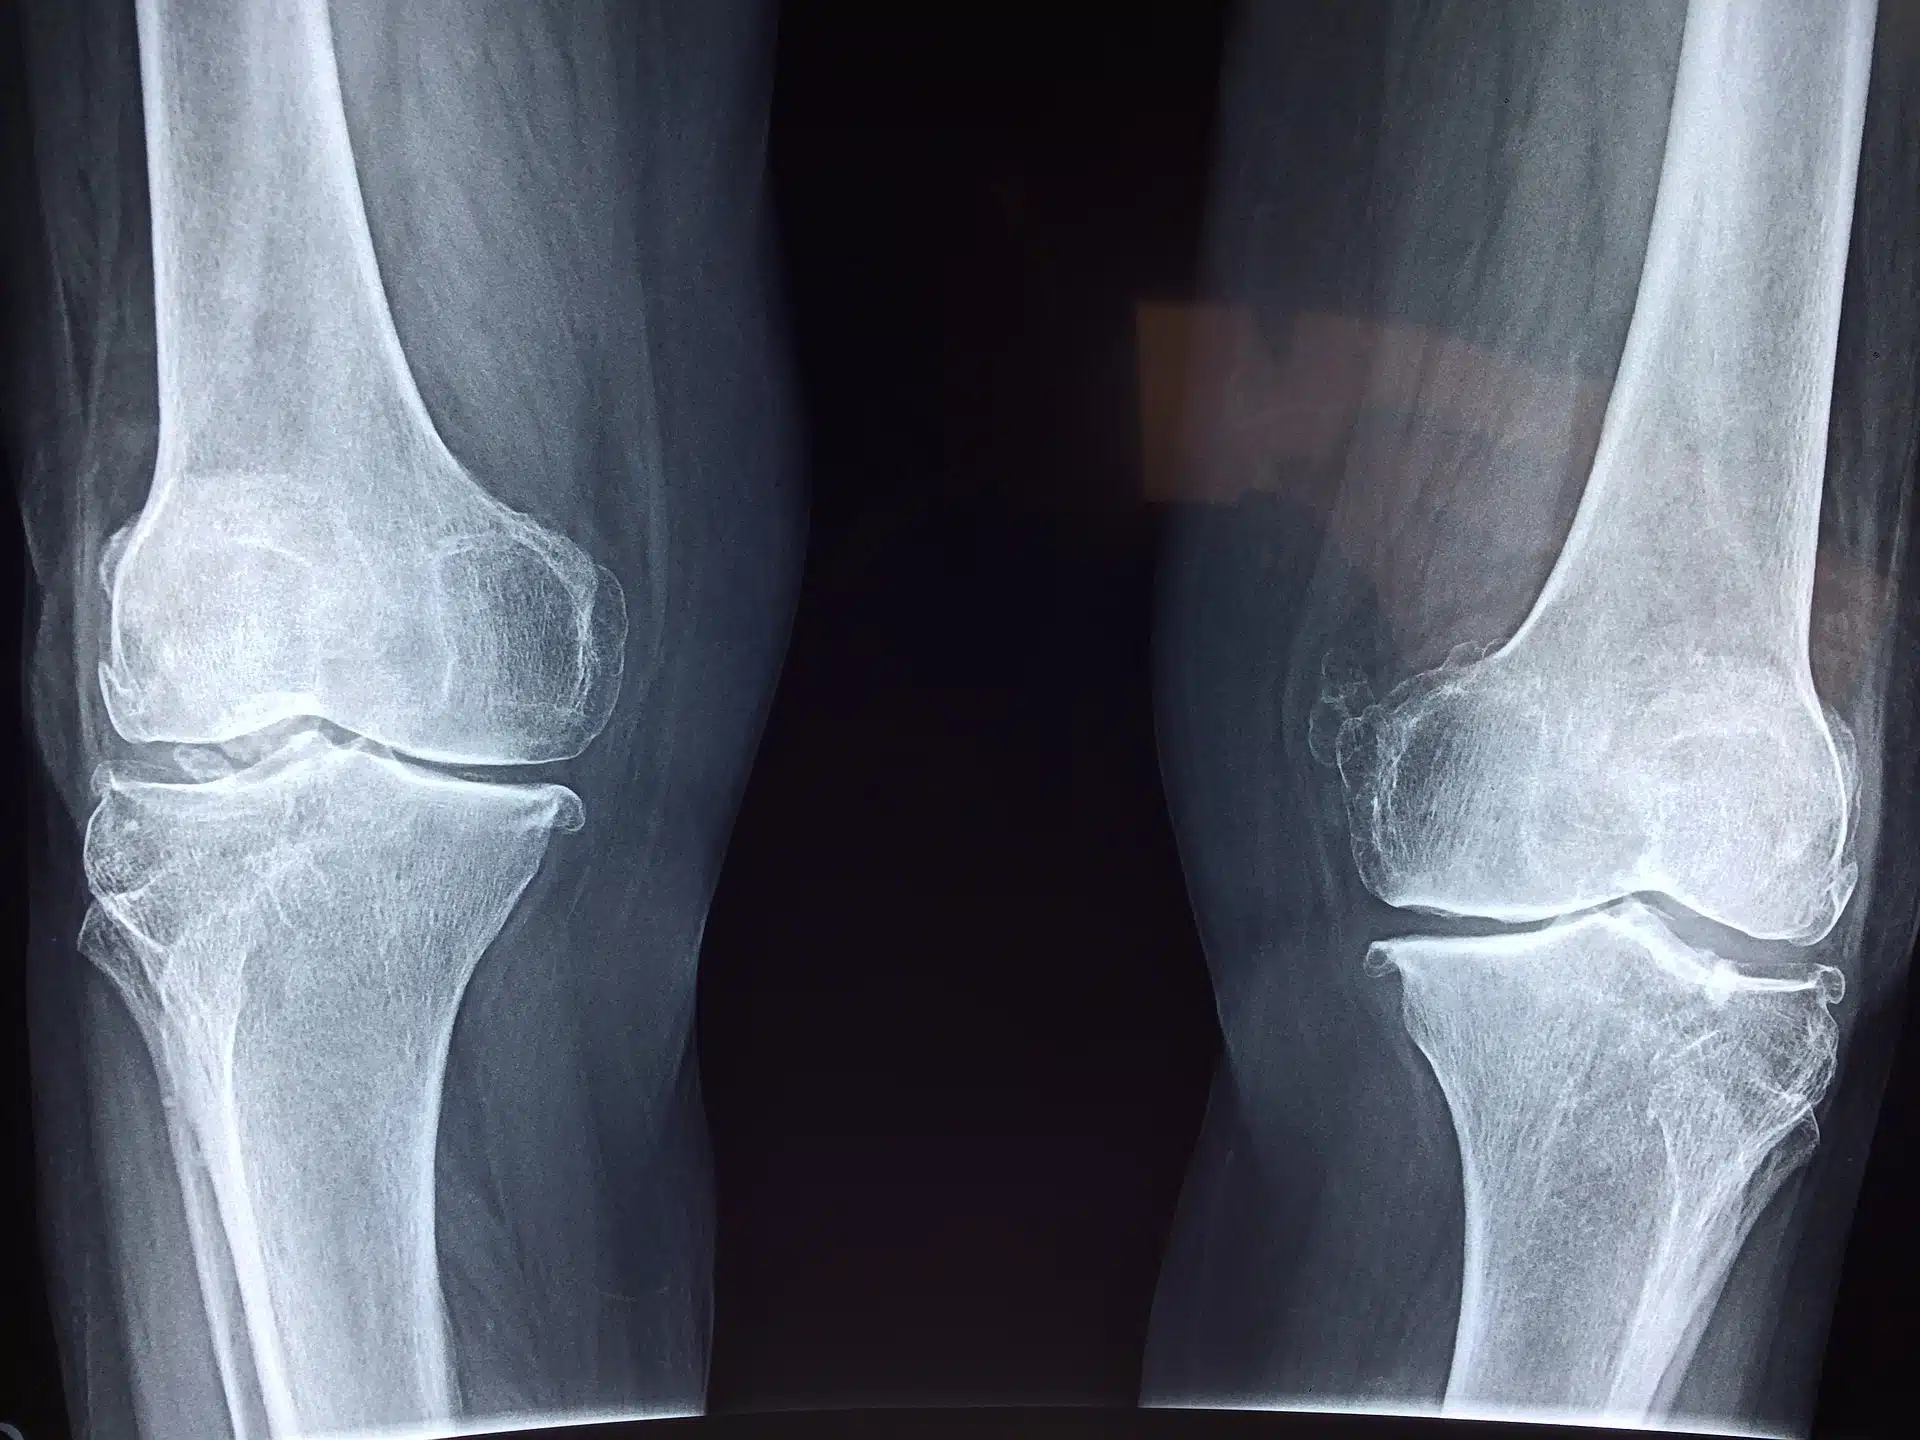

پزشک ارتوپد در معاینه زانو ،محدوده حرکتی زانو، قدرت زانو و پایداری مفصل زانو را بررسی میکند . همچنین از رادیو گرافی زانو نیز بهره می برد تا متوجه شدت آسیب به مفصل زانو گردد . اگر بیمار معیارهای کافی برای نیاز به جراحی آرتروپلاستی زانو یا عمل جراحی تعویض مفصل زانو داشته باشد، این عمل به بیمار توصیه خواهد شد.

– آرتروز پوکی استخوان یا استئوآرتریت یک بیماری است که بیشتر افراد میانسال و سالخورده را درگیر میکند و ممکن است باعث شکسته شدن غضروف مفصل و استخوان مجاور در زانو شود. آسیب به غضروف و استخوان حرکت را محدود میکند و باعث درد میشود.

– آرتروز ورم مفاصل یا آرتریت روماتوئید، که باعث التهاب مایع غشایی مفاصل میشود، میتواند منجر به درد و سفتی گردد.

– آسیب مفاصل به دلیل حوادث و تصادفات، نیز ممکن است باعث ایجاد آسیب به غضروف زانو شود. شکستگی، پاره شدن غضروف و یا رباط ها، احتمال ایجاد آسیب جبران ناپذیر در مفصل زانو میکند.